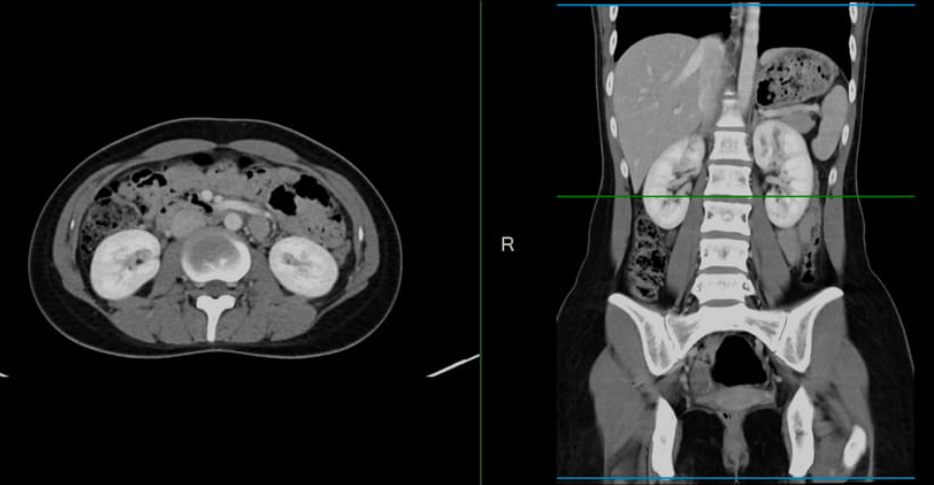

Computed tomography (CT) scans are effective for detecting some types of cancer. The CT scanner captures images of the individual’s insides while they lie on a table. The computer assembles the images of what’s happening beneath the skin to create 3D representations that enable medical professionals to identify tumors and other health issues.

The tube sends out multiple beams of radiation, which capture images of what’s happening inside your body. The images are then assembled to produce 3D representations, providing medical professionals with a clear view of your organs, bones, and blood vessels. These 3D images can reveal tumors and enable professionals to measure masses.

A screening test produces accurate images of your bones, blood vessels (typically when using contrast dye), and organs. These images can reveal growths and masses. Since the images are three-dimensional, it’s possible to measure any growth. The size and location of tumors detected enable doctors to determine what type of cancer it is and what stage you’re in. This information helps them determine the best treatment options.